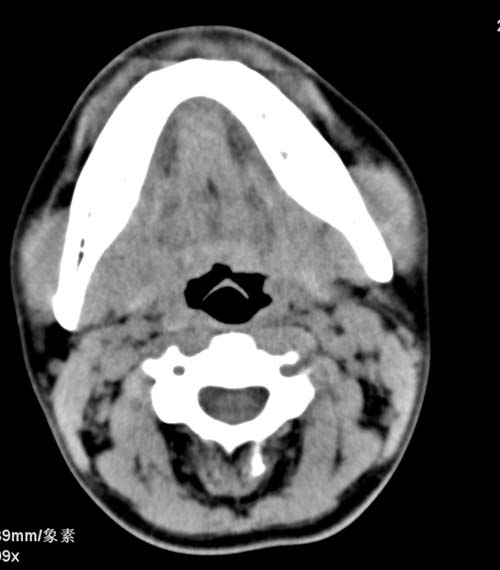

标题: CT22662:女 23 自述双侧颌下腺肿大年余 近来疼痛 左侧明显 [打印本页]

标题: CT22662:女 23 自述双侧颌下腺肿大年余 近来疼痛 左侧明显

见双侧颌下腺略肿大  未见结石及钙化 考虑双侧慢性炎症 ?请指教